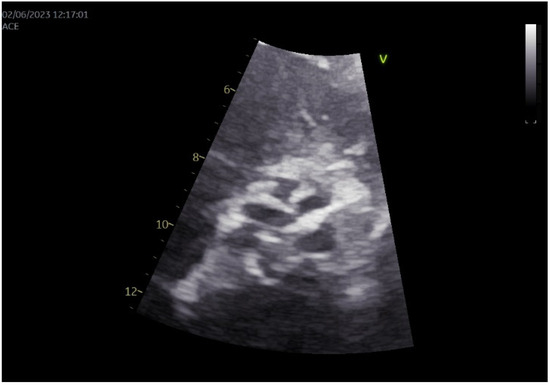

Simultaneous Endovascular Abdominal Aortic Aneurysm Repair and Open Repair of Common Femoral Artery Aneurysm: Short Case Series and Current Review

Background: Common femoral artery aneurysms are rare and are usually associated with aneurysms at other sites, mainly the aorta, iliac, popliteal, superficial femoral, and profunda femoral artery. This combination poses the challenge of synchronous repair for clinically relevant aneurysms. Although endovascular abdominal aortic [...] Read more.

Background: Common femoral artery aneurysms are rare and are usually associated with aneurysms at other sites, mainly the aorta, iliac, popliteal, superficial femoral, and profunda femoral artery. This combination poses the challenge of synchronous repair for clinically relevant aneurysms. Although endovascular abdominal aortic aneurysm repair is the main type of treatment for abdominal aortic aneurysms nowadays, this is not true for common femoral aneurysms, where open repair remains the gold standard. These two distinct operations could be combined in a one-stage procedure when aortoiliac and common femoral aneurysms present simultaneously. This approach potentially saves time and costs, without increasing complications. Methods: A retrospective search was conducted in the Vascular Surgery Department database of a tertiary referral center for vascular surgery, covering procedures from January 2005 to May 2025. Patients were included if they had undergone simultaneous endovascular abdominal aortic aneurysm repair and open repair of a common femoral artery aneurysm. Clinical records, operative details, imaging studies, and follow-up data were reviewed. We additionally provide a literature review regarding this approach. This review additionally incorporates the current knowledge regarding the treatment of common femoral artery aneurysms. Results: Out of 668 endovascular abdominal aortic aneurysm repair procedures, three patients (0.45%) were identified. These three patients were among five patients who were treated for true common femoral artery aneurysm by open repair in the same time interval. All of the patients are currently in good condition without late complications. One patient, who had not performed any follow-up imaging, was diagnosed with large aneurysms at other sites, 10 years later. Conclusions: The combined one-stage endovascular abdominal aortic repair and open repair of a common femoral artery aneurysm by interposition grafting is technically a simple approach that led to satisfactory outcomes. Full article

Show Figures

Figure 1